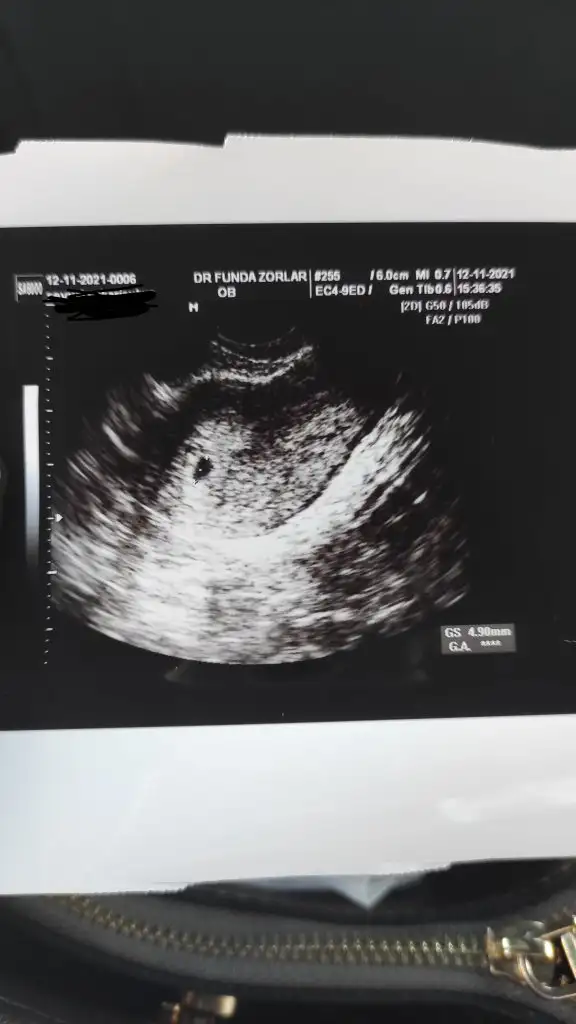

12 Kasım 2513.42 çıktı. Doktor ağrılar normal ama daha önce düşüğün olduğu için riske girmeyelim dedi iğne verdi. Vajinal ultrasonda keseyide gördükBenim miniğime bi bakın bakalım. Bir de beta hcg sanki biraz yüksek gibi sat 10 ekim onu da anlamadım.